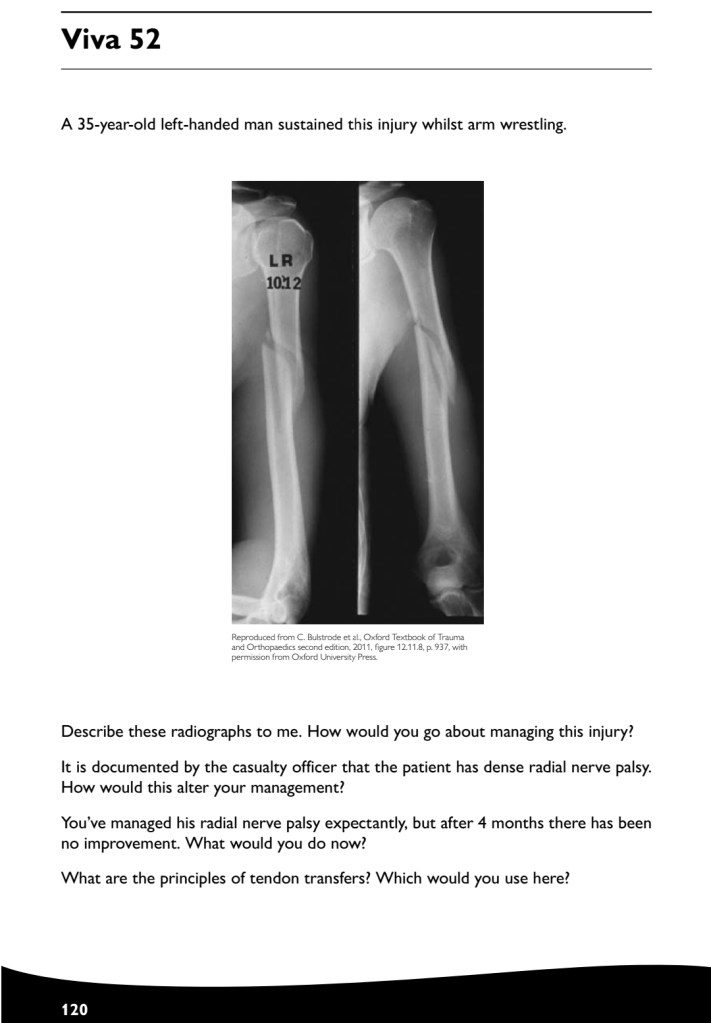

Revision how to answer your case